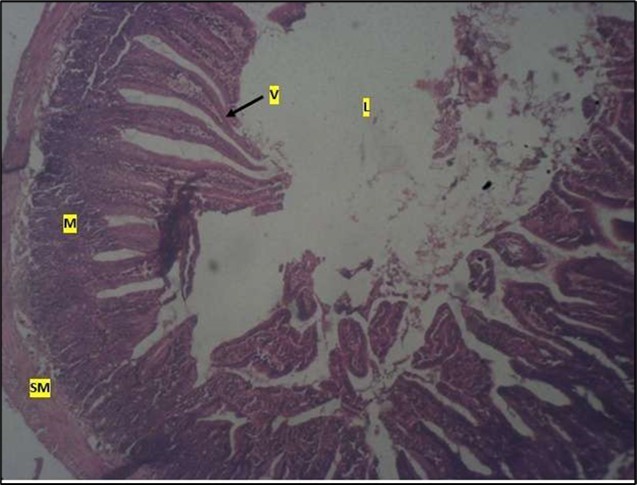

Histological examination of the small intestine result in control animals revealed a normal architecture with the red pulp and white pulp with no pathological observation Figure 2. Administration of Abelmoschus esculentus at low dose shows an increased cellularity with numerous cells in the Mucosa and the villi projecting towards the lumen. Focal metaplasia of mucosal cells alongside villous disruption was also observed (Figure 3). The high dose group showed normal cellular architecture with no villous disruption (Figure 4).

Figure 4.High dose showing a normal mucosa (m) with villi (v) projecting towards the lumen(l) and underlying smooth muscle layer (sm). No pathology seen